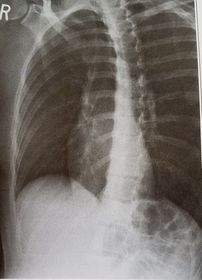

| AP Shoulder | patient is rotated towards the unaffected shoulder: decreased thoracic superimposition over the scapular body |

| AP Shoulder | patient is rotated towards affected side:increased thoracic superimposition over the scapular body |

| Oblique Sternum | projection taken as LAO instead of RAO sternum is projected within the heart and scapula |

| RAO Sternum | inadequate breathing technique |

| Lateral Sternum | patient's left thorax is rotated anteriorly |

| Lateral Sternum | patient's right thorax is rotated anteriorly |

| PA Ribs Above Diaphragm Unilateral | patient rotated towards the right |

| PA Ribs Below Diaphragm Unilateral | Excessive obliquity |

| AP - LPO Ribs Above Diaphragm Unilateral | Insufficient obliquity |